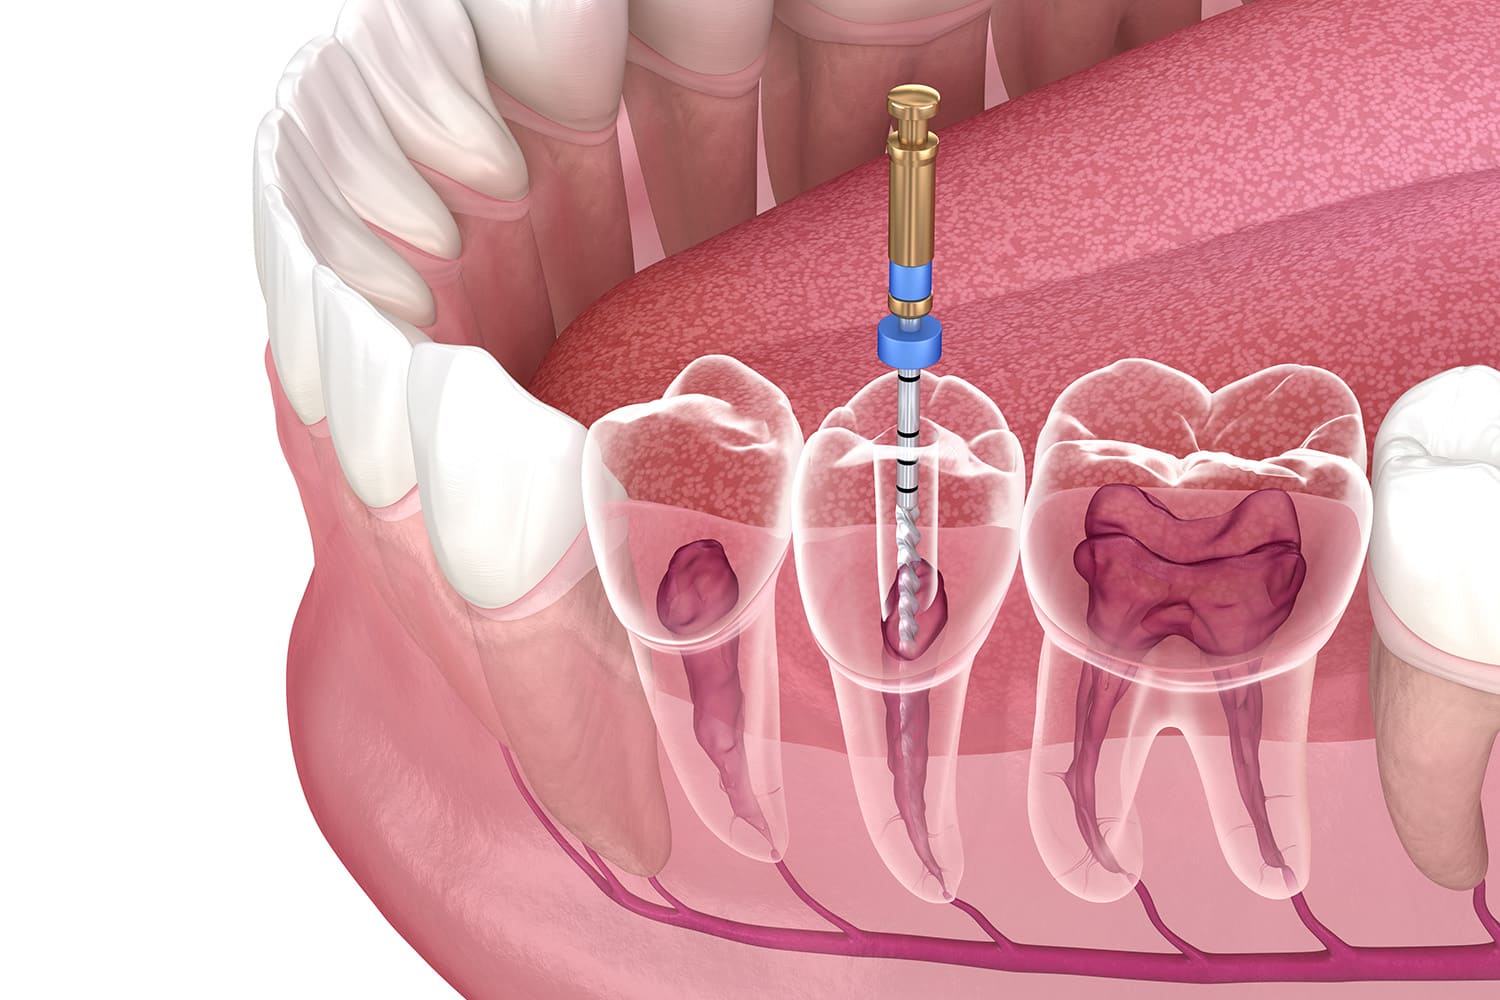

虫歯治療は、進行度に応じて適切な処置を行います。初期はフッ素塗布や経過観察、進行すると虫歯部分を削り詰め物で補修します。重度の場合は神経の治療が必要になることもございます。痛みを抑えた治療を心掛け、再発防止のため定期検診やケア指導も行います。